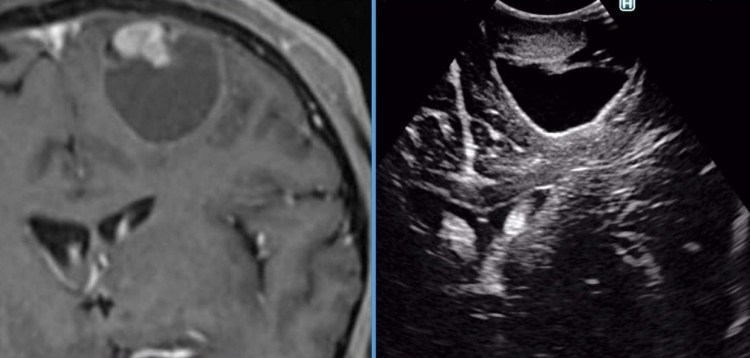

–Meduloblastoma: Tumor originado a partir de células primitivas neuroectodérmicas. Pesenta un alto componente proliferativo (grado IV de la OMS). Tiene lugar en la fosa posterior, característicamente en el techo del cuarto ventrículo, si bien no es rara la localización en hemisferio cerebeloso en adultos jóvenes. Puede dar lugar a la siembra a través del neuroeje, incluso a metástasis fuera del sistema nervioso central. Es frecuente la presencia de hidrocefalia obstructiva en el momento del diagnóstico. Ésta puede precisar una intervención quirúrgica previa a la extirpación del tumor. El tratamiento del meduloblastoma se basa en la extirpación quirúrgica seguida de radio y quimioterapia. Presenta una tasa de curación elevada en los casos en los que no hay diseminación y la cirugía logra eliminar por completo o reducir al mínimo la carga tumoral.